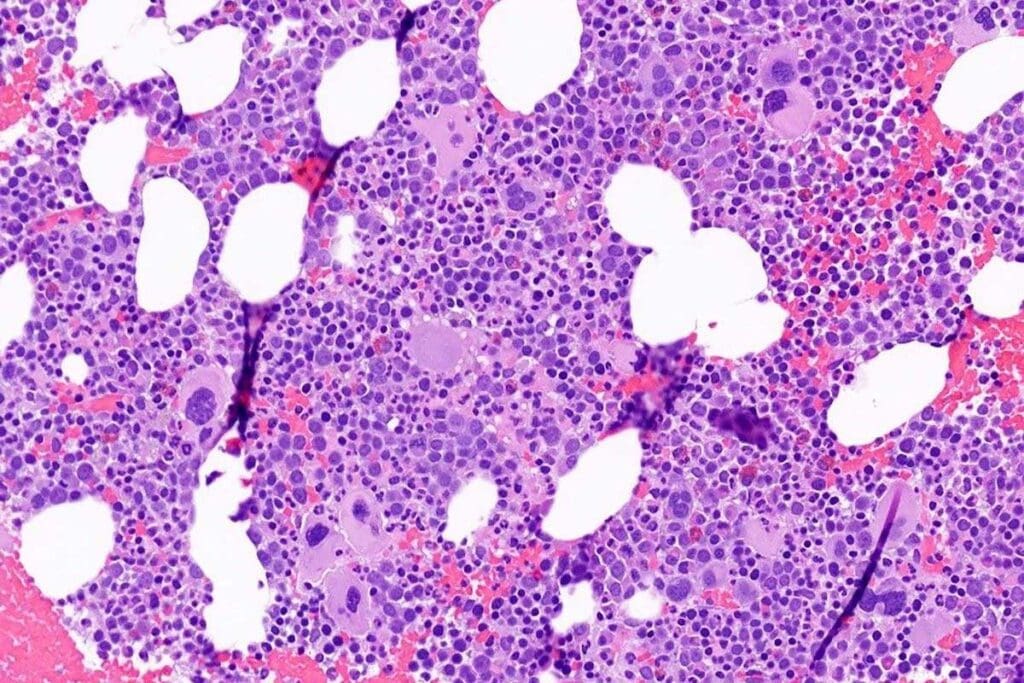

Bone Marrow Biopsy and Aspiration

A bone marrow biopsy and aspiration are key for SAA diagnosis. These take a bone marrow sample for study. In SAA, the marrow has fewer cells than usual.